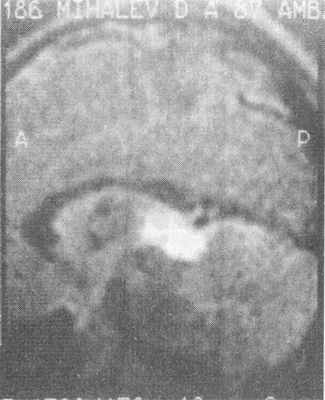

Краниальные ХГЧ-секретирующие герминативно-кпеточные опухоли являются достаточно частой причиной ППР у мальчиков. В европейских странах частота этих опухолей у детей составляет от 0,3 до 3,4% от всех опухолей головного мозга, в Японии - от 4,8 до 15%. Наиболее типичная локализация - пинеальная область, реже встречаются опухоли, локализующиеся в области супраселлярной цистерны. Выявляются эти образования при проведении КТ и МРТ головного мозга в виде плотного, хорошо накапливающего контраст образования. Достаточно часто опухоль содержит кальцификаты (рис. 7). Гистологически герминативно-клеточные опухоли могут быть представлены чистыми гермино- мами и тератомами. До 30% герминативно-клеточных опухолей имеют злокачественный характер.

Рис. 7. МР-томограмма ХГЧ-секретирующей герминомы эпифиза